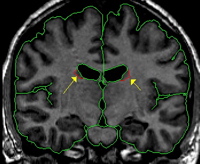

|  | Posteriorly, it is often difficult to get a useful histogram, so intensity contour can be employed.